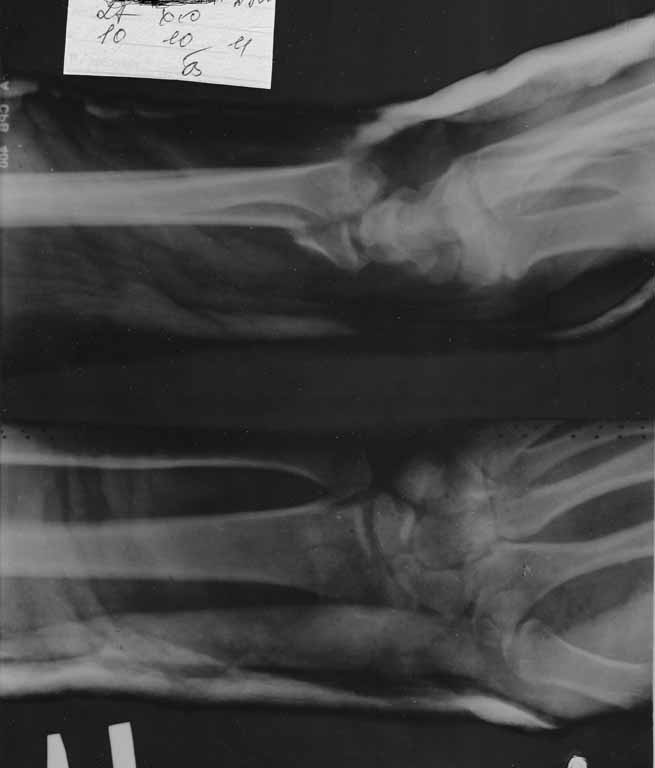

Виктор! А локтевая у Вас не в вывихе?

Нет не в вывихе, т. К. Из-за спицы проведенной через обе кости предплечья, то ротационные движения и подвижность локтевой кости резко ограничены, это может в некоторых проекциях расцениваться как подвывих, если найду покажу финальный снимок, там все рентгенологические показатели восстановлены.